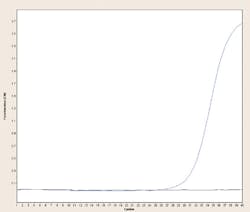

In practice, HDA doesn’t produce as much target amplification as a well optimized PCR reaction. However, in a one-hour reaction, it can still yield 107 or greater amplification factor. For many applications, particularly in infectious agent-detection settings, this is more than enough sensitivity, and HDA reactions capable of detecting a few hundred target copies per reaction are quite possible.

Detection of the HDA product can be done by any of the means used to detect PCR products, including endpoint analysis (for example, by gels or arrays) or by fluorescent based real-time methods. In keeping with the instrumental simplicity of HDA, however, most currently available commercial diagnostics based on this technique employ a simple variation on the instrumentation-free, visually readable “line probe assay” approach (to be covered in next month’s column on alternate detection strategies). This combination of a very simple but powerful and specific isothermal amplification strategy and a simple, disposable, instrumentation-free detection system brings a molecular diagnostic tool functionally closer to point of care (POC) testing than ever before—even if it is still constrained from that designation at present for regulatory reasons.